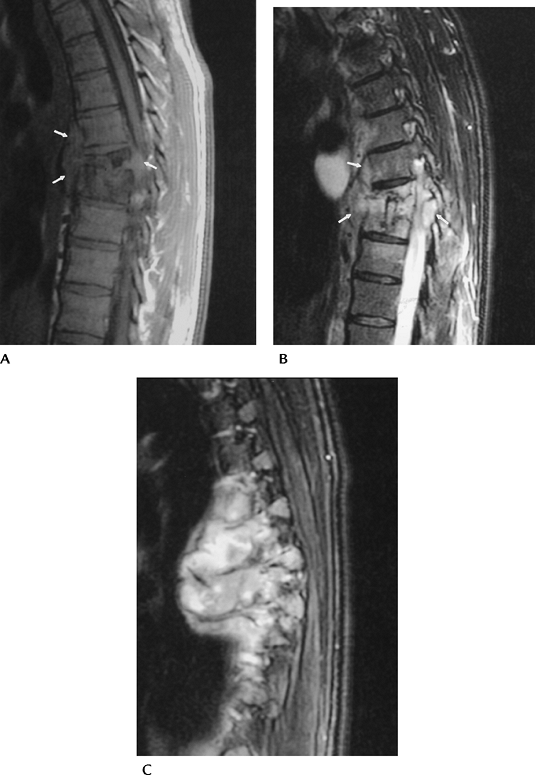

FIGURE 3-58 Tuberculous spondylitis in the thoracic spine. Sagittal T1-weighted (A) and T2-weighted (B) images demonstrate disc space loss and vertebral compression with paravertebral soft tissue extension (arrows). Off-axis sagittal image (C) shows a large multiloculated paraspinal abscess.